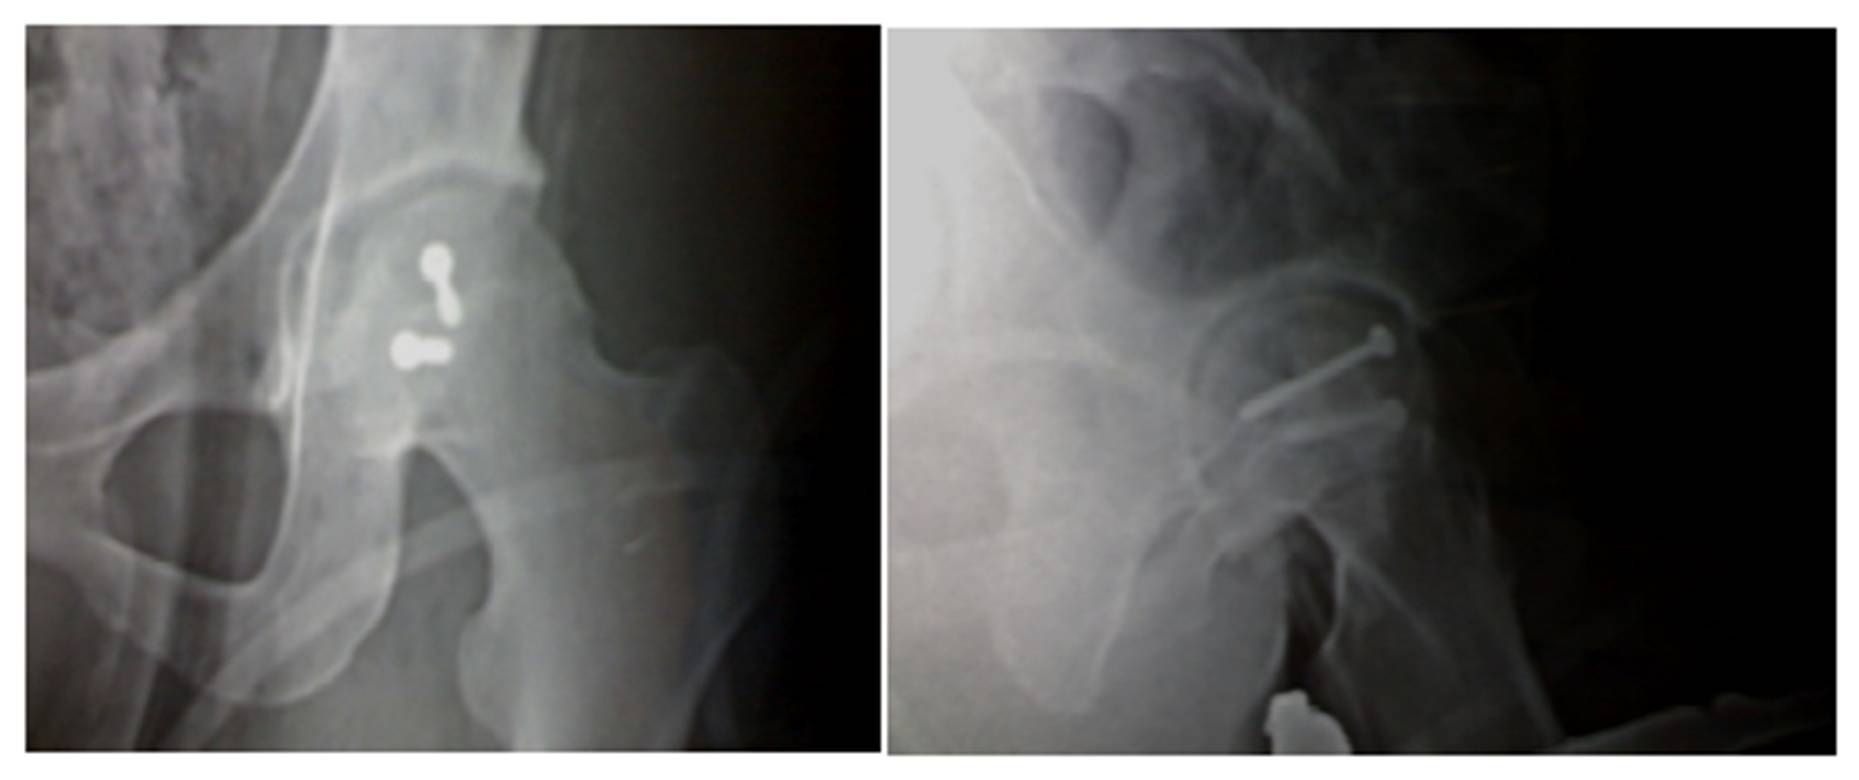

Figure 14

Case (3): The X-ray shows avascular necrosis and hip sublaxation after the posterior approach used for ORIF of femoral head fracture.